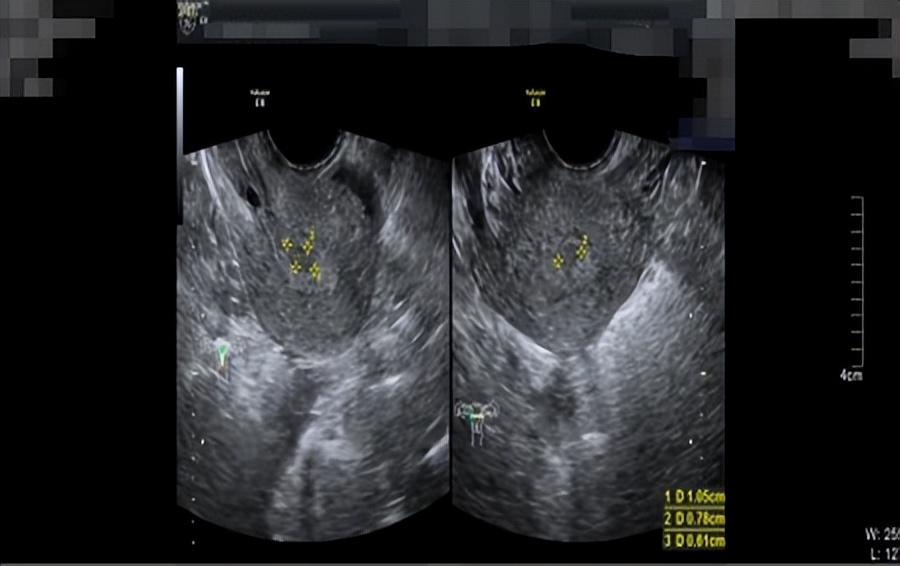

周女士十分焦虑,她问我:“医生,我之前流产过一次,然后现在我又一直出血,我以后不会不能怀孕了吧?我还没有结婚,我还想生个孩子,医生,你一定要帮帮我”我对周女士说:“我们会尽力的”我的内心能够感受到周女士迫切的心情,我想子宫对一个未孕女子的意义重大,我们作为医者,一定要从患者的切身角度去维护好患者最大的意愿。我查阅周女士的病历了解到,周女士在2021年8月初的时候就诊医院B超检查子宫,超声提示内膜厚1.8cm(双层),回声不均,考虑子宫内膜厚,如图1所示,当时给予黄体酮口服12天,情况缓解。在2021年9月,月经第5天时复查,超声提示内膜增厚1.29cm(双层),回声不均,宫腔内见1.1*0.8*0.6cm稍低回声,内见星点状血流,息肉?粘肌?如图2所示。

图2.复查黄体酮治疗后B超结果